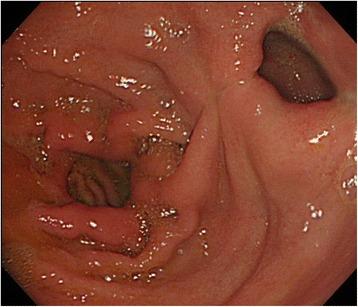

An 80-year-old female with advanced gastric cancer and pyloric stenosis was admitted to Kagoshima University Hospital. As peritoneal washing cytology produced a positive result, laparoscopic gastrojejunostomy (modified Devine procedure) was performed to improve food passage, and S-1 (100 mg/body, days 1-14) plus paclitaxel (120 mg/body, days 1 and 15) was administered. Although the tumor was temporarily reduced in size, an abdominal computed tomography scan obtained after four courses of chemotherapy showed progressive disease. Thus, chemoradiotherapy (56 Gy, S-1: 60 mg/body, CDDP: 5 mg/body, days 1-5) was indicated. Marked tumor shrinkage and negative peritoneal washing cytological results were achieved. Curative gastrectomy with D2 lymphadenectomy was performed. We carried out distal gastrectomy and lymph node dissection, and the gastrojejunostomy produced as a gastric bypass in the previous operation was preserved. The patient has not suffered a tumor relapse in 4 years since the surgery.